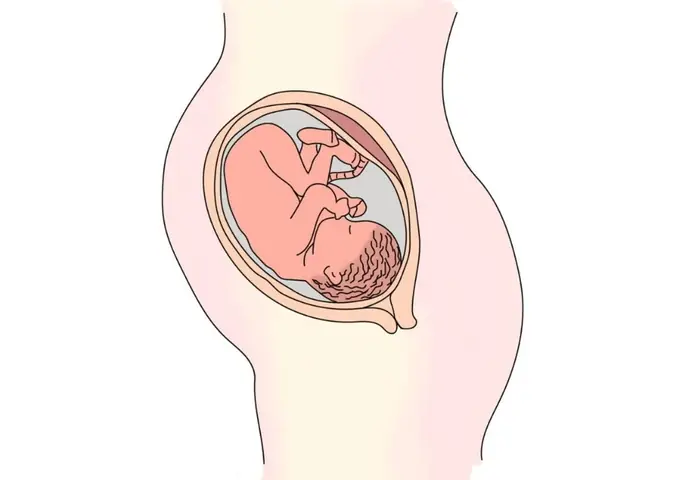

Khi bước vào tháng thứ 7 của thai kỳ, mẹ bầu đang ở giai đoạn tam cáp cuối cùng, giai đoạn mà thai nhi có những thay đổi lớn về mặt thể chất lẫn chức năng. Đây là thời điểm mà bé có nhiều chuyển biến đáng kinh ngạc, từ việc hoàn thiện các cơ quan nội tạng cho đến việc hình thành các phản xạ và thói quen. Việc tìm hiểu về hình ảnh thai nhi tháng thứ 7 không chỉ giúp mẹ bầu hình dung rõ hơn về sự phát triển của con yêu mà còn giúp mẹ chuẩn bị tâm lý và sức khỏe tốt nhất cho những tuần cuối thai kỳ. Bài viết này sẽ cung cấp những thông tin chi tiết, đáng tin cậy về hình ảnh thai nhi tháng thứ 7, sự phát triển của bé, những thay đổi của cơ thể mẹ, cũng như các chăm sóc và lưu ý quan trọng mà mẹ cần biết trong giai đoạn này.

Hình ảnh thai nhi tháng thứ 7 cho thấy một em bé đã có hình dạng gần như hoàn chỉnh, trông giống một em bé sơ sinh. Khi bước vào tuần thứ 28, thai nhi đã dài khoảng 35-38 cm và nặng khoảng 1-1.2 kg. Bé đã có đầy đủ các chi, ngón tay, ngón chân, khuôn mặt cũng đã rõ ràng với mũi, mắt, miệng, tai. Tuy nhiên, làn da của bé vẫn còn mỏng, nhăn nheo và có thể nhìn thấy các mạch máu dưới da. Điều này là do lớp mỡ dưới da chưa phát triển đầy đủ.

Các ngón tay và ngón chân của thai nhi đã có vân tay riêng biệt, và bé có thể nắm tay, đưa tay lên miệng. Móng tay đã bắt đầu mọc dài ra khỏi ngón tay, và tóc trên đầu cũng bắt đầu mọc. Một số bé có thể có tóc dày và đen, trong khi một số bé khác thì tóc thưa và nhạt màu. Điều này phụ thuộc vào yếu tố di truyền.

Hình ảnh thai nhi tháng thứ 7 cho thấy các cơ quan nội tạng đã phát triển gần như hoàn chỉnh. Phổi là cơ quan quan trọng nhất cần được theo dõi trong giai đoạn này, vì đây là thời điểm bé bắt đầu luyện tập hô hấp. Các phế nang trong phổi bắt đầu tiết ra chất surfactant, một chất giúp phổi mở rộng và hoạt động hiệu quả sau khi sinh. Tuy nhiên, phổi của bé vẫn chưa hoàn toàn trưởng thành, vì vậy nếu bé sinh non vào tháng thứ 7, bé có thể cần được hỗ trợ hô hấp.

Tim của thai nhi cũng đã phát triển mạnh mẽ, đập khoảng 120-160 lần mỗi phút. Hệ tiêu hóa đã bắt đầu hoạt động, bé có thể nuốt nước ối và thải ra phân su, một chất màu xanh đen tích tụ trong ruột non. Hệ thần kinh trung ương tiếp tục phát triển, não bộ tăng trưởng nhanh chóng, các tế bào thần kinh hình thành các kết nối phức tạp. Bé đã có thể cảm nhận ánh sáng, âm thanh, và thậm chí có thể phân biệt được giọng nói của mẹ.

Hình ảnh thai nhi tháng thứ 7 cho thấy bé đã có nhiều chuyển động và phản xạ. Bé có thể đạp, đá, xoay người, và thậm chí có thể mút ngón tay. Những chuyển động này không chỉ giúp bé rèn luyện cơ bắp mà còn giúp phát triển hệ thần kinh. Mẹ bầu có thể cảm nhận rõ ràng các chuyển động của bé, và có thể nhận ra các mẫu chuyển động lặp đi lặp lại, như một thói quen.

Bé cũng bắt đầu hình thành các phản xạ quan trọng, như phản xạ mút, phản xạ nắm tay, và phản xạ Moro (phản xạ giật mình). Những phản xạ này rất quan trọng cho sự sống sót của bé sau khi sinh. Ngoài ra, bé cũng bắt đầu có giấc ngủ và thức, có thể phân biệt giữa ngày và đêm.

Hình ảnh thai nhi tuần 28 cho thấy một em bé đã dài khoảng 35-38 cm và nặng khoảng 1-1.2 kg. Bé đã có đầy đủ các chi, ngón tay, ngón chân, khuôn mặt cũng đã rõ ràng. Làn da của bé vẫn còn mỏng và nhăn nheo, nhưng đã bắt đầu có lớp mỡ dưới da. Bé có thể nắm tay, đưa tay lên miệng, và bắt đầu có các chuyển động mạnh mẽ.

Hình ảnh thai nhi tuần 29 cho thấy bé đã dài khoảng 38-40 cm và nặng khoảng 1.2-1.4 kg. Bé đã có thể mở mắt và nhắm mắt, và có thể cảm nhận ánh sáng. Bé cũng đã có thể nghe được các âm thanh từ bên ngoài, như giọng nói của mẹ, tiếng nhạc, hoặc các âm thanh khác. Bé có thể phản ứng lại các âm thanh bằng cách đạp hoặc chuyển động.

Hình ảnh thai nhi tuần 30 cho thấy bé đã dài khoảng 40-42 cm và nặng khoảng 1.4-1.6 kg. Bé đã có thể mút ngón tay, và có thể nuốt nước ối. Bé cũng đã có thể thải ra phân su, một chất màu xanh đen tích tụ trong ruột non. Bé có thể có các giấc ngủ và thức, và có thể phân biệt giữa ngày và đêm.

Hình ảnh thai nhi tuần 31 cho thấy bé đã dài khoảng 42-44 cm và nặng khoảng 1.6-1.8 kg. Bé đã có thể mở mắt và nhìn xung quanh, và có thể cảm nhận ánh sáng. Bé cũng đã có thể nghe được các âm thanh từ bên ngoài, và có thể phản ứng lại các âm thanh bằng cách đạp hoặc chuyển động. Bé có thể có các thói quen, như mút ngón tay hoặc đá chân.